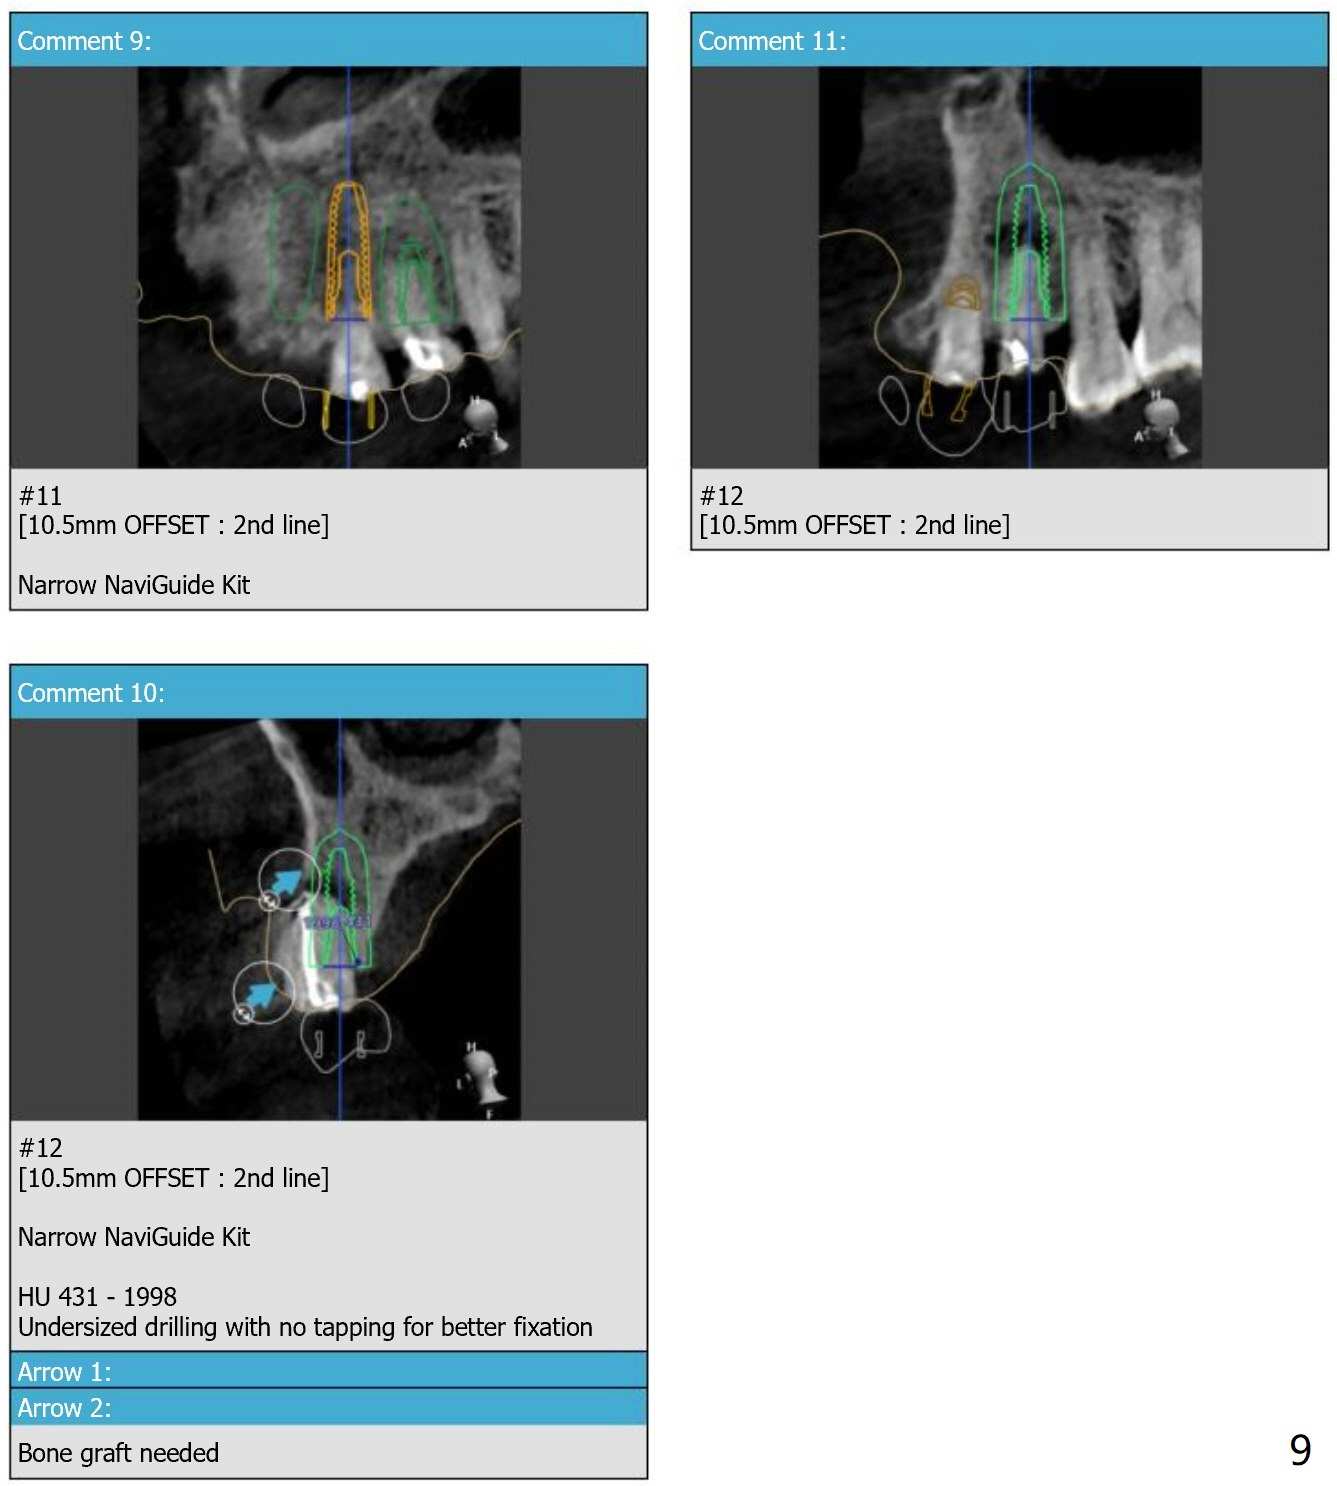

Since the apex of the tooth #5 seems to tilt mesial, implants at #6 and 7 will be placed mesial intentionally with diameters of 3.5 and 3 mm (Fig.1-3). On the left side with minor space issue, two-piece implants with 3.5 mm in diameter will be placed at #11-12 (Fig.5-6). After implant osteointegration, a 4-unit FPD will be fabricated between #7-10. Return to Upper Arch Immediate Implant, Trajectory, Metronidazole Xin Wei, DDS, PhD, MS 1st edition 11/09/2018, last revision 11/16/2018